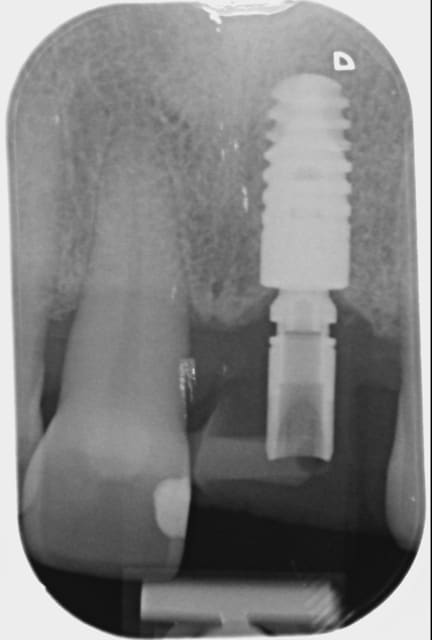

05/08/2014 à 11h23

Comme demandé en MP voici le contrôle 10 mois après la pose.

C'est acceptable je pense. Ce traitement a ses limite bien sûr mais peut être une indication voire une alternative dans certains cas spécifiques comme celui-ci.

Au passage, qui connait le nom que l'on donne à cette collerette de GA que l'on voit sur 13-12-11-22-23, j'ai oublié.

A omtjjz - Eugenol

1 zf3owi - Eugenol

Img 0812 mvp6i0 - Eugenol

jeamba

05/08/2014 à 20h20

Je ne sais pas si tu as réellement ingressé car quad je regarde ta radio du départ et celle que tu viens de mettre, ton apex arrive pratiquement au même niveau de spire, à savoir au niveau de la troisième spire en partant de l'apex de l'implant. Il y a quelque chose qui m'échappe.